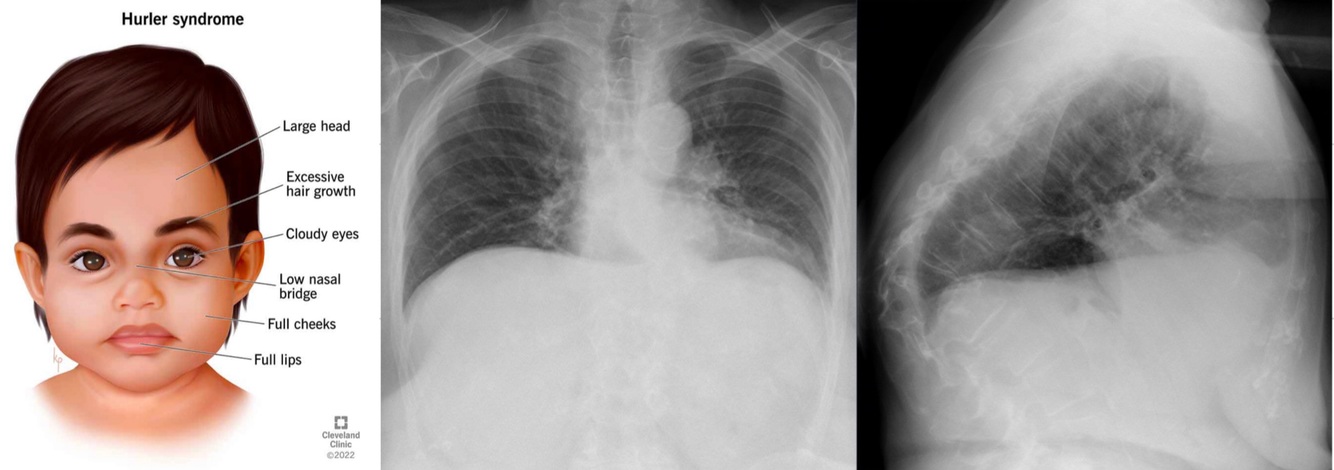

Clinical presentation of untreated severe MPS 1 (Hurler) by age? (4)

At birth: non-specific, umbilical or inguinal hernia, frequent URI

By 1 year: coarse facial features, Gibbus deformity, progressive skeletal dysplasia

By 3 year: intellectual disability, hearing loss, corneal clouding

Death by 10 years of life without treatment

Onset between 1-10 years

Hearing loss

Corneal clouding

Respiratory involvement

Cardiac valvular disease